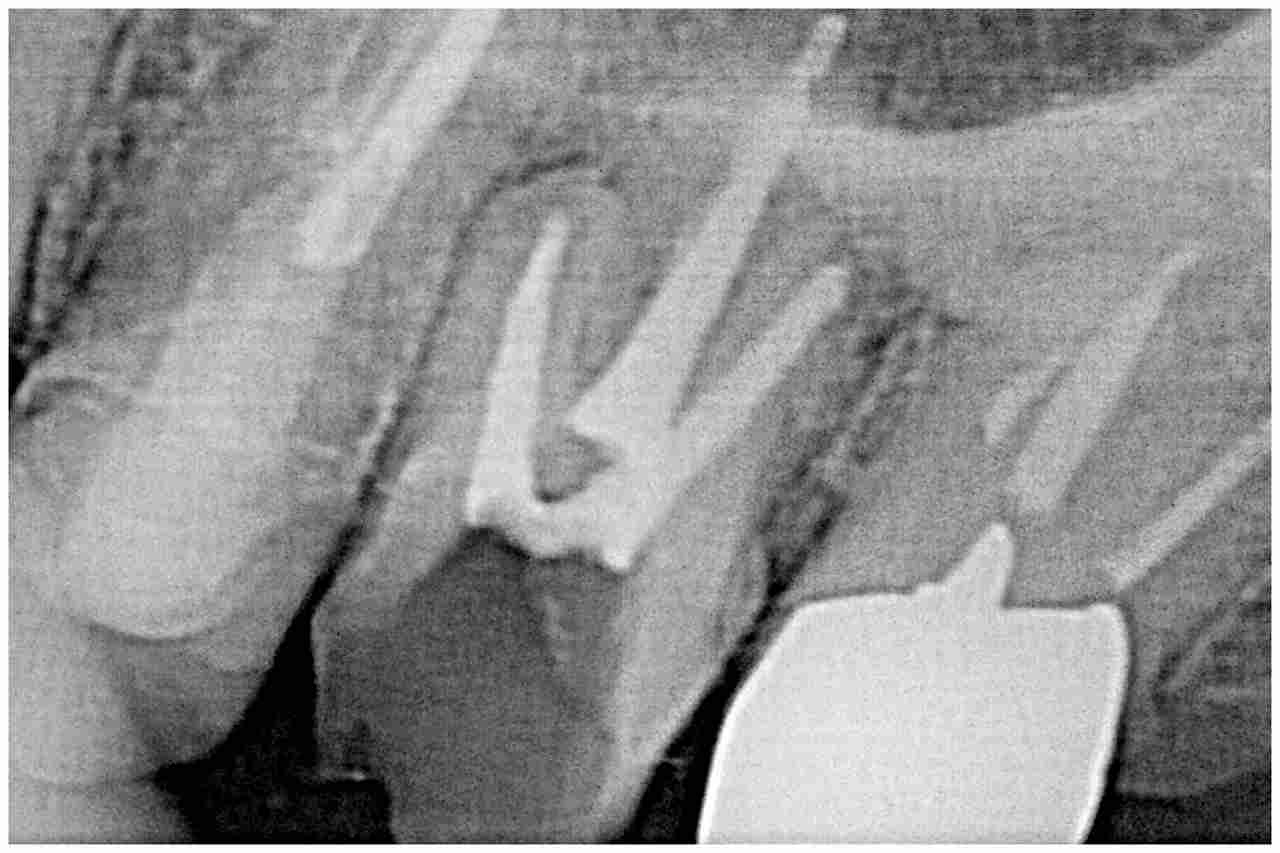

6番は近心部から見ても穴が開いています

大きく虫歯になっていました

根の治療から行いました

根充後、ファイバーコアにて土台を立てています